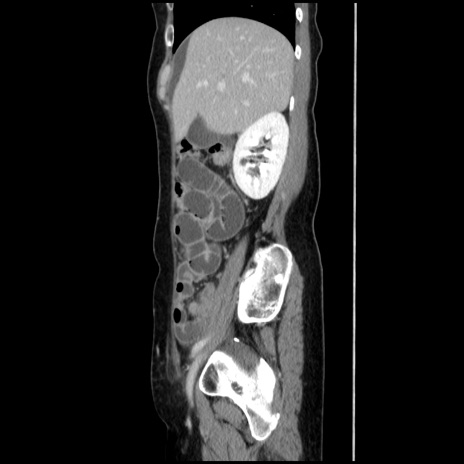

横断像

【症例】40歳代 女性

【主訴】上腹部痛、嘔気・嘔吐

【現病歴】約9時間前頃から急に上腹部痛、嘔気、嘔吐が出現。改善しないため救急要請。

【既往歴】子宮頚癌(広汎子宮全摘術、放射線療法)、腸閉塞

【身体所見】腹部:平坦、軟、腸雑音亢進、上腹部を中心に腹部全体に圧痛あり。

【データ】WBC 8400、CRP 0.03